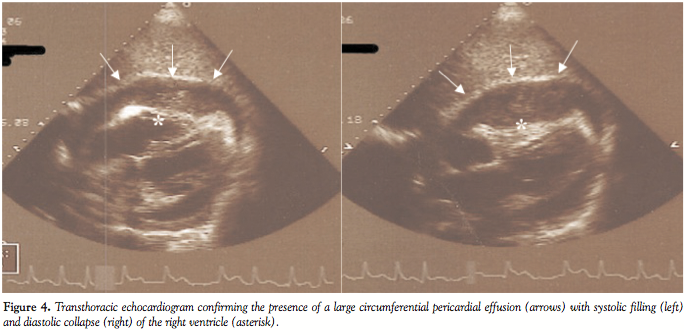

The patient was initiated on intravenous antibiotics with broad-spectrum coverage, fluid resuscitation with normal saline, and intravenous rate control with diltiazem infusion. Computed tomography angiography of the chest

revealed no evidence of pulmonary emboli, but demonstrated a large pericardial effusion and small bilateral pleural effusions (Figure 3). Bedside transthoracic echocardiogram confirmed the presence of a large circumferential pericardial effusion with diastolic collapse of the right ventricle (Figure 4) with marked respiratory variation of mitral and tricuspid inflow velocities, and plethora of the inferior vena cava verifying the clinical diagnosis of cardiac tamponade.